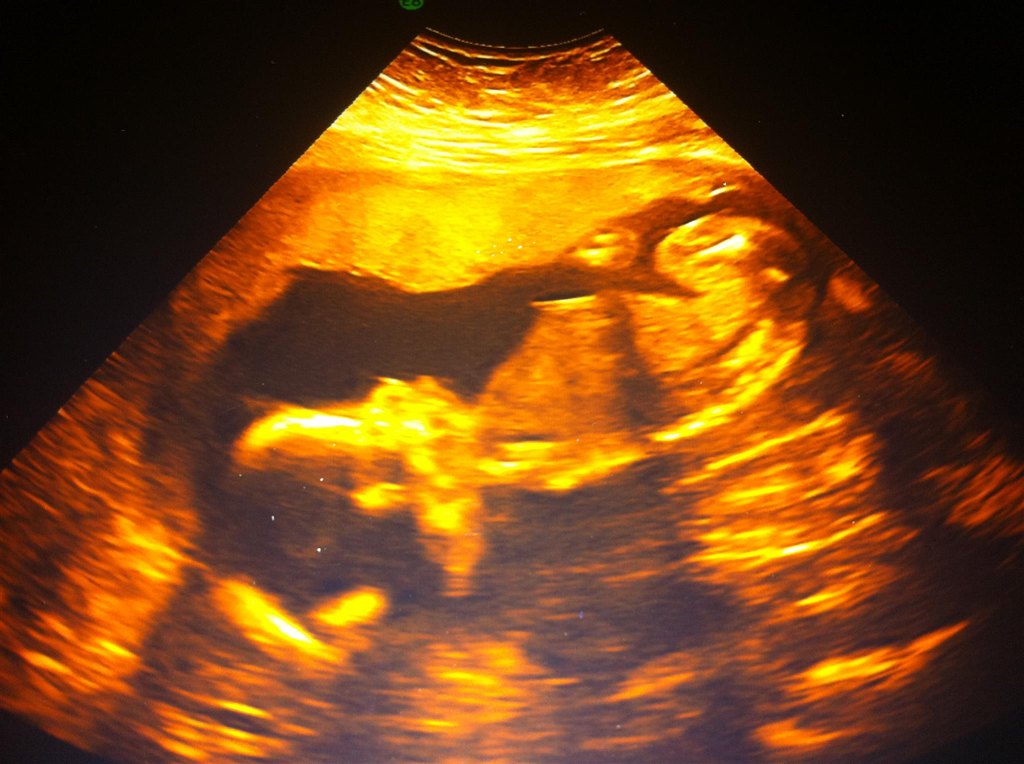

Hehe ja det ER da en lille søhest... eller måske en havfrue/mand...

Og tillykke med den veloverståede scanning!

Vi fik mega dårlige billeder til den oprindelige MD sidste uge, men DEM her, de var fanme også dårlige...

Dem fra NF er klart de bedste